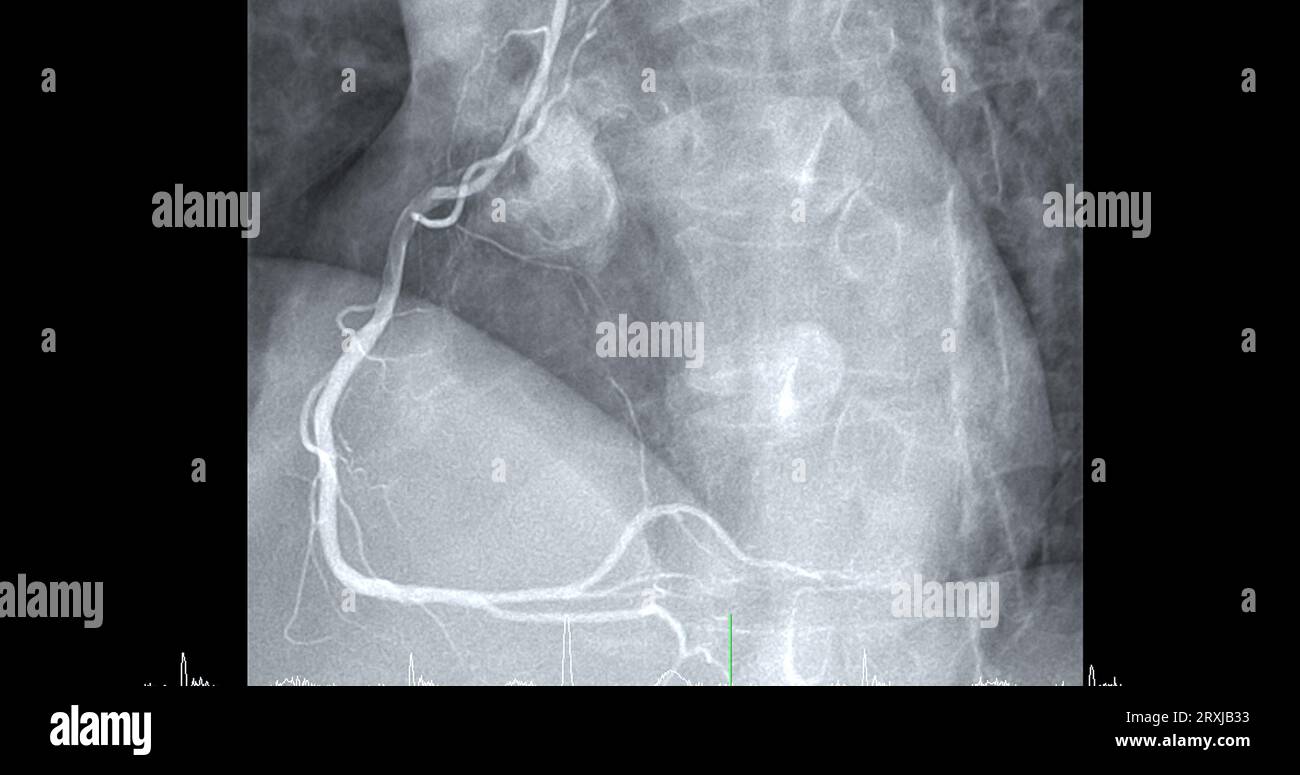

From www.alamy.com

Cardiac catheterization on right coronary artery (RCA) can help doctor Heart Catheterization Blocked Artery cardiologists use a procedure called cardiac catheterization to see how well your heart is working. doctors may suspect you have blocked arteries in your heart (coronary artery disease) if: Angioplasty is often followed by the. This is a pressure management method that’s used in catheterization to see how much blockage is in an artery. a cardiac cath. Heart Catheterization Blocked Artery.